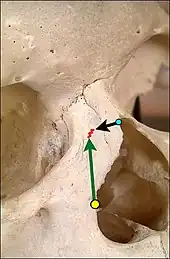

F. Bony anatomy of the nose

In the upper portion of the nose, the paired nasal bones attach to the frontal bone. Above and to the side (superolaterally), the paired nasal bones connect to the lacrimal bones, and below and to the side (inferolaterally), they attach to the ascending processes of the maxilla (upper jaw). Above and to the back (posterosuperiorly), the bony nasal septum is composed of the perpendicular plate of the ethmoid bone. The vomer bone lies below and to the back (posteroinferiorly), and partially forms the choanal opening into the nasopharynx, (the upper portion of the pharynx that is continuous with the nasal passages). The floor of the nose comprises the premaxilla bone and the palatine bone, the roof of the mouth.

The nasal septum is composed of the quadrangular cartilage, the vomer bone (the perpendicular plate of the ethmoid bone), aspects of the premaxilla, and the palatine bones. Each lateral nasal wall contains three pairs of turbinates (nasal conchae), which are small, thin, shell-form bones: (i) the superior concha, (ii) the middle concha, and (iii) the inferior concha, which are the bony framework of the turbinates. Lateral to the turbinates is the medial wall of the maxillary sinus. Inferior to the nasal conchae (turbinates) is the meatus space, with names that correspond to the turbinates, e.g. superior turbinate, superior meatus, et alii. The internal roof of the nose is composed by the horizontal, perforated cribriform plate (of the ethmoid bone) through which pass sensory filaments of the olfactory nerve (cranial nerve I); finally, below and behind (posteroinferior) the cribriform plate, sloping down at an angle, is the bony face of the sphenoid sinus.

In relation to the nasal bone (teal green), seven bones compose the orbit.

(1) the frontal bone (yellow)

(2) the lacrimal bone (green)

(3) the ethmoid bone (brown)

(4) the zygomatic bone (blue)

(5) the upper jaw maxillary bone (purple)

(6) the palatine bone (aqua)

(7) the sphenoid bone (red)